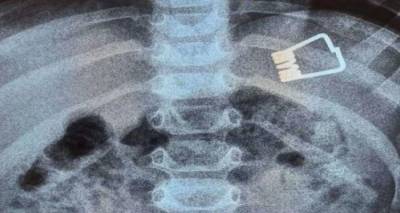

Αγοράκι δύο ετών από τη Λήμνο κατάπιε έλασμα από μανταλάκι. Για την απίστευτη περιπέτεια που ξεκίνησε από ένα παιχνίδι για να καταλήξει σε έναν αγώνα με τον χρόνο μίλησε αποκλειστικά στο LIVE NEWS ο πατέρας του παιδιού.